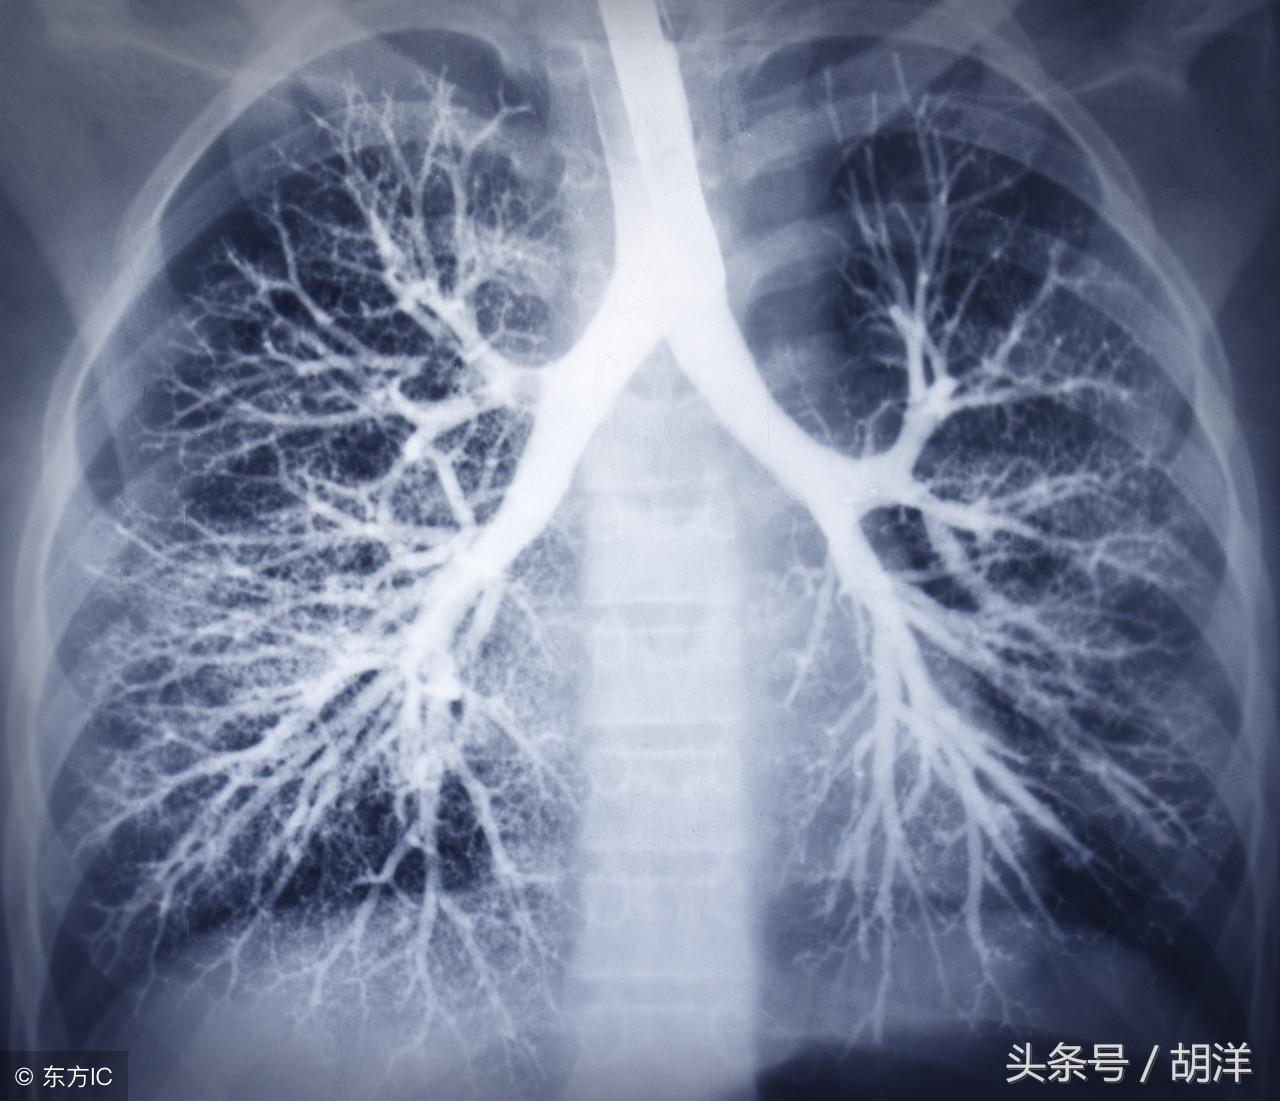

支气管扩张

支气管扩张是一种支气管管壁结构破坏性疾病,正常情况下,支气管是一个带有弹性,拥有一定管径的能够维持正常呼吸通气的结构,当管壁结构受到破坏时,气管会受到被动的牵拉而扩张,管壁的血管由于弹性较小,容易被撕扯呈血管瘤改变,一旦胸腔内血流压力增大可能冲破血管瘤变薄的管壁而导致大咯血,少量渗血时则呈现为痰中带血。